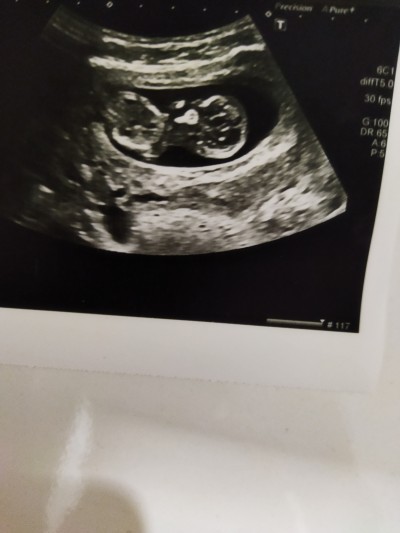

Merhaba cinsiyet ne zaman öğrendiniz bize bı doktor kız gibi bacak arası boş dedi başka doktor erkek bacak arası dolu dedi

anlayanlr yorum yapabilir mi

Gebelik haftası 12 hafta